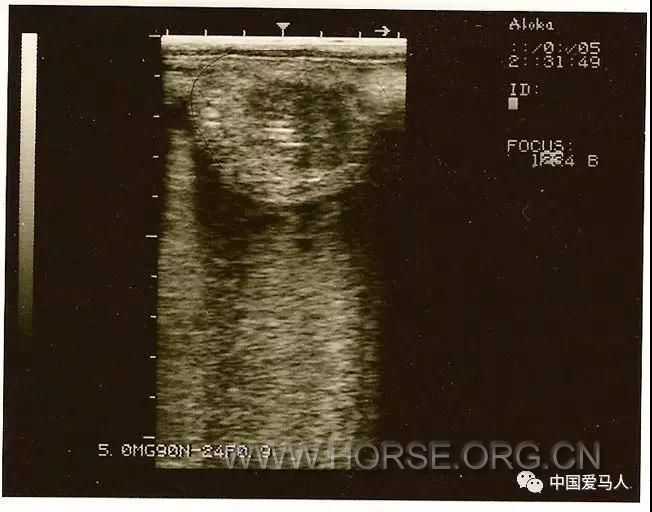

图 母体子宫体的超声图像显示明显的水肿模式。

图 可见为子宫中的“沙钱”或“橙片”图像。出现这种图像是因为此时子宫的变化特征。子宫有几个子宫内膜褶皱,增加子宫内膜的表面积。在发情期间,这些褶皱充满了液体,使该区域呈现橙色切片的外观。